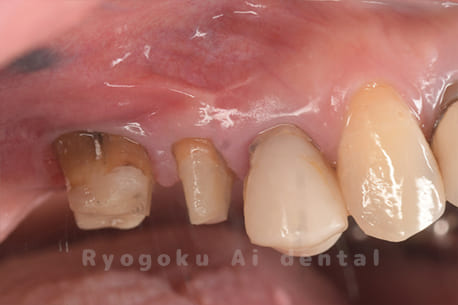

Case14

-

- 抜歯原因

- 重度カリエス

- 治療内容

- クラウンレングスニング治療

- 治療費用

- 44,000円

他院で抜歯と言われた、とのことでご来院された患者さまです。クラウンレングスニングを行い、保存致しました。大変満足して頂けました。

<リスク・副作用>

治療後、痛みや違和感、出血、腫れなどが出る事があります。喫煙者、糖尿病などの方の場合、歯が生着しない場合があります。